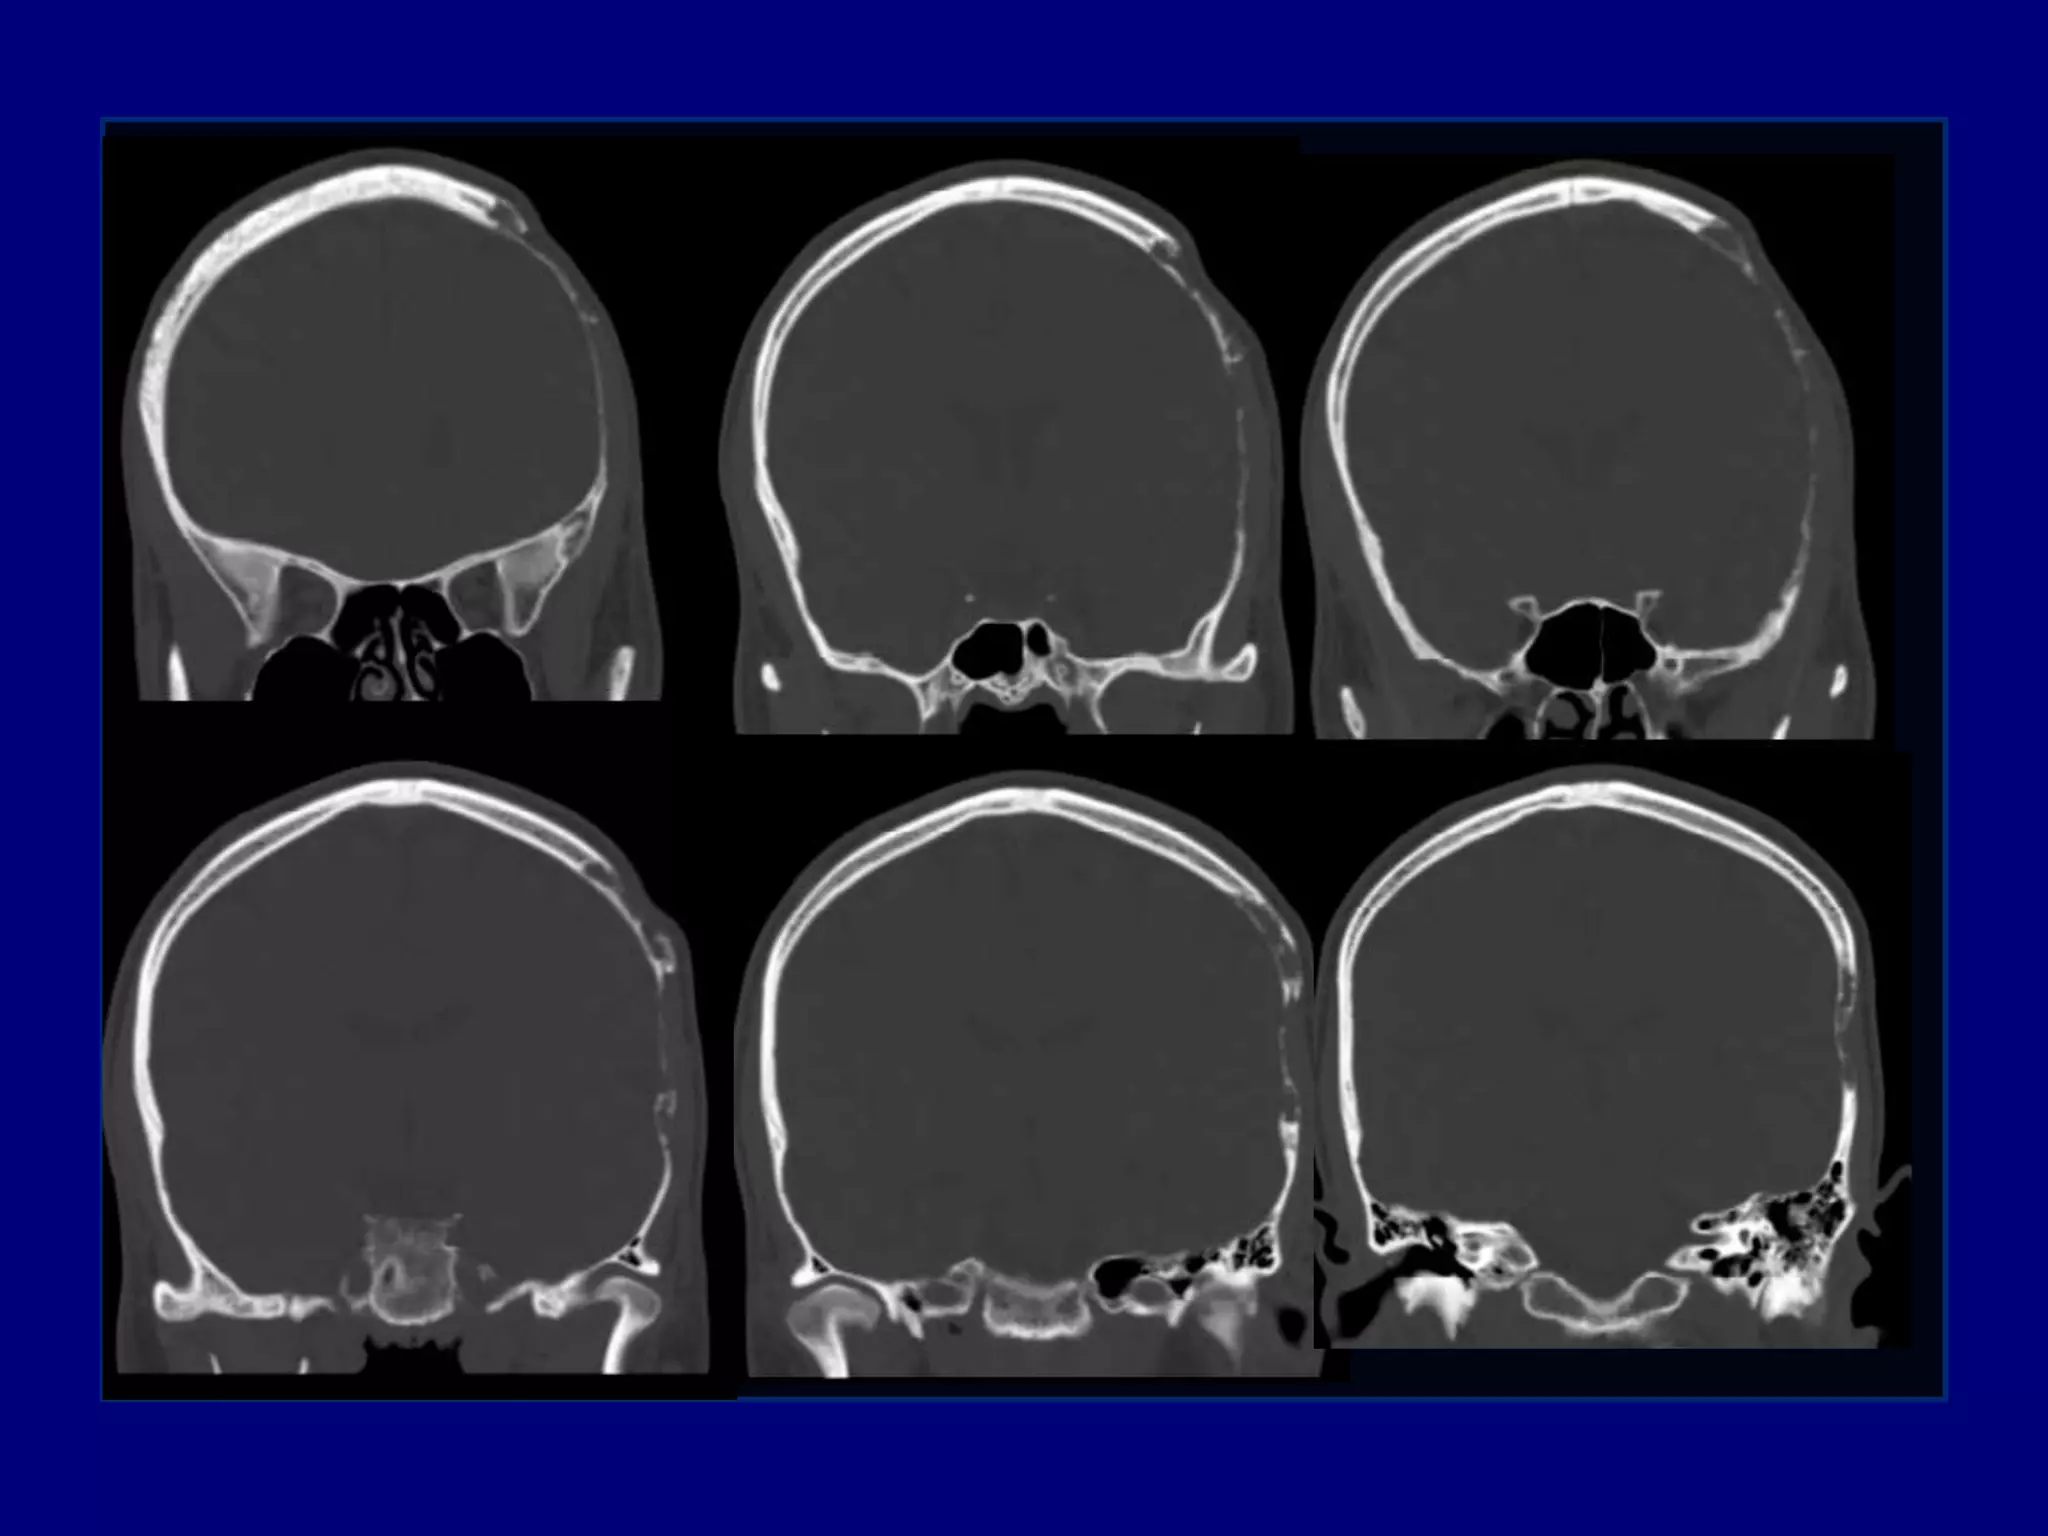

Computed Tomography

Magnetic Resonance Imaging

Imaging

CT

Well defined skull defect with benign characteristics

 Thinning and disappearance of central portion and

absence of new bone formation